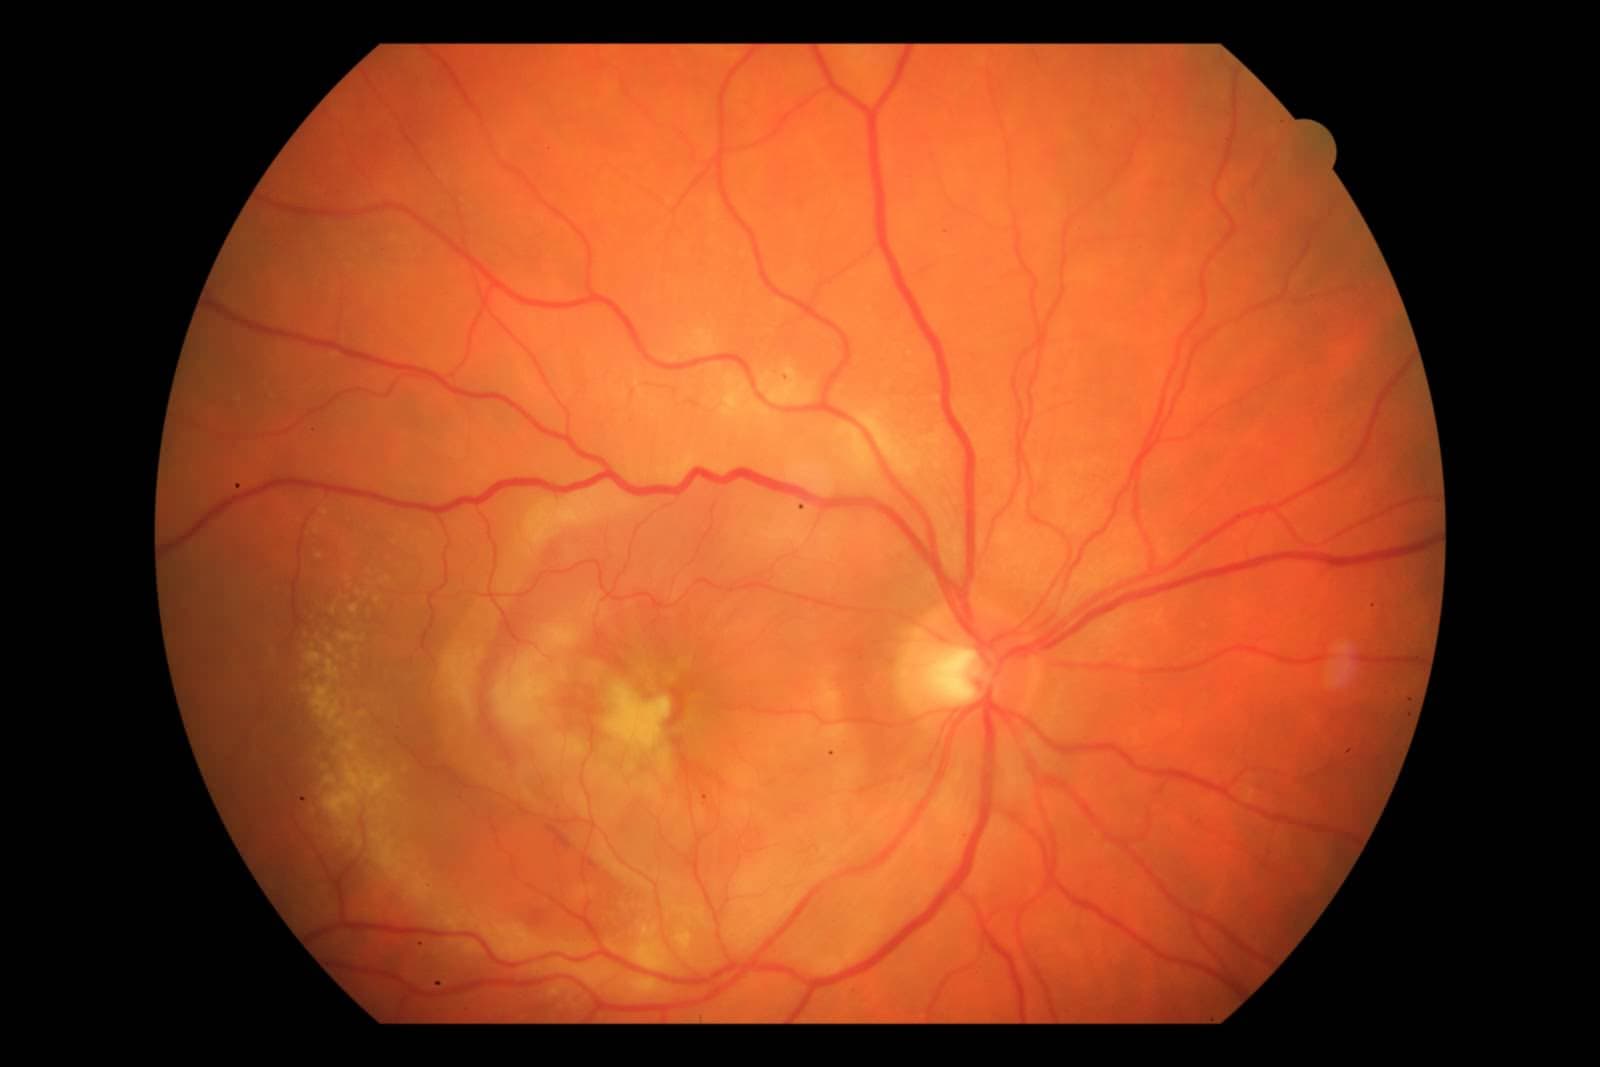

Makula Dejenerasyou Tedavisi

Gözün görme merkezinin (makula) hasarı genel olarak 2 grupta incelenirler: Juvenil Makula Dejenerasyonları Çocuklarda görülen, genellikle hayatın ilk...